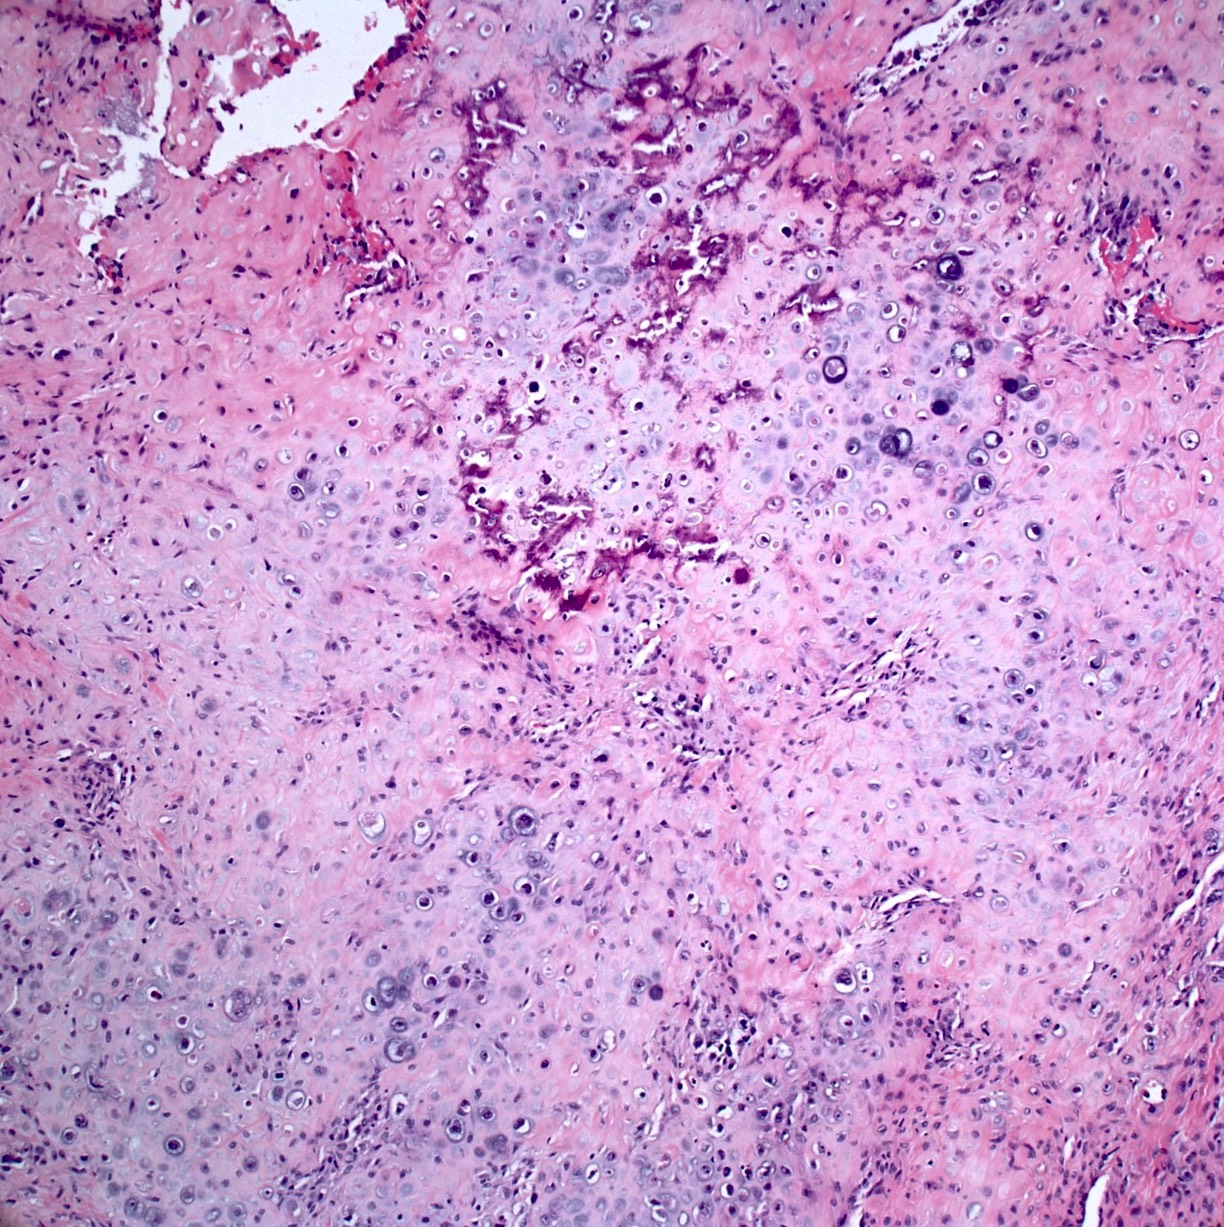

Microscopic (histologic) images

Contributed by Jesse Hart, D.O., Borislav A. Alexiev, M.D. and AFIP

- Status postneoadjuvant chemotherapy:

- Report treatment response as a percent tumor necrosis (really an assessment of tumor drop out)

- Edematous scar: loose edematous to myxoid granulation tissue, fibrosis, mild chronic inflammation

- Bony matrix remains

- Residual tumor cells: nests of tumor cells in retraction clefts are common

- Grading response to chemotherapy (same cutoffs as Ewing sarcoma) (Cancer 1993;72:3227, J Clin Oncol 1988;6:329):

- Good response is > 90% tumor necrosis

- Report treatment response as a percent tumor necrosis (really an assessment of tumor drop out)

- Assessment of preoperative chemotherapy:

- Preoperative chemotherapy is commonly used with limb salvage procedures for treatment of high grade sarcomas, particularly osteosarcoma and Ewing sarcoma

- It is generally required to quantify the extent of tumor necrosis as a percentage of the total tumor area

- For osteosarcomas, chemotherapy induced necrosis of ≥ 90% has a > 90% disease free survival, compared with < 50% in patients with < 90% tumor necrosis

- To determine the extent of necrosis in an osteosarcoma or Ewing sarcoma specimen, the slab specimen of the resected bone containing tumor provides the template for histologic analysis

- Photograph of the slice is taken and the site of each numbered block is marked on a grid pattern diagram